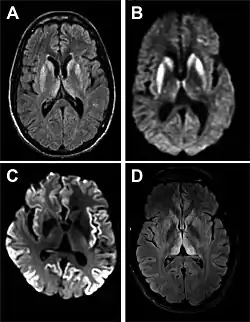

- MRI with diffusion weighted inversion (DWI) and fluid-attenuated inversion recovery (FLAIR) shows a high signal intensity in certain parts of the cortex (a cortical ribboning appearance), the basal ganglia, and the thalami.[42] The most common presenting patterns are simultaneous involvement of the cortex and striatum (60% of cases), cortical involvement without the striatum (30%), thalamus (21%), cerebellum (8%) and striatum without cortical involvement (7%). In populations with a rapidly progressive dementia (early in the disease process), MRI has a sensitivity of 91% and specificity of 97% for diagnosing CJD.[46] The MRI changes characteristic of CJD may also be seen in the immediate aftermath (hours after the event) of autoimmune encephalitis or focal seizures.[42]

Imaging of the brain may be performed during medical evaluation, both to rule out other causes and to obtain supportive evidence for diagnosis. Imaging findings are variable in their appearance and also variable in sensitivity and specificity.[49] While imaging plays a lesser role in diagnosis of CJD,[50] characteristic findings on brain MRI in some cases may precede onset of clinical manifestations.[51]

Brain MRI is the most useful imaging modality for changes related to CJD. Of the MRI sequences, diffuse-weighted imaging sequences are most sensitive.[52] Characteristic findings are as follows:

- Focal or diffuse diffusion-restriction involving the cerebral cortex or basal ganglia. The most characteristic and striking cortical abnormality has been called "cortical ribboning" or "cortical ribbon sign" due to hyperintensities resembling ribbons appearing in the cortex on MRI.[53] The involvement of the thalamus can be found in sCJD, is even stronger and constant in vCJD.[54]

- Varying degree of symmetric T2 hyperintense signal changes in the basal ganglia (i.e., caudate and putamen), and to a lesser extent globus pallidus and occipital cortex.[50]